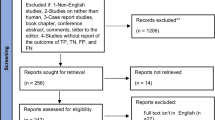

Aneurysm (Rupture of blood vessels) may happen in the cerebrum, abdominal aorta and thoracic aorta of humans, which has a high fatal rate. The advancement of the artificial technologies specifically machine learning algorithms and deep learning models have attempted to predict the aneurysm, which may reduce the death rate. The main objective of this paper is to provide the review of various algorithms and models for the early prediction of the various types of aneurysms. The focused literature review was conducted from the preferred journals from 2007 to 2022 on various parameters such as way of collecting images, the techniques used, number of images used in data set, performance metrics and future work. The summarized overview of advances in prediction of aneurysms using the machine learning algorithms from non linear kernel support regression algorithm to 3D Unet architecture of deep learning models starting from CT scan images to final performance analysis in prediction. The range of sensitivity, specificity and area under receiving operating characteristic was from 0. 7 to 1 for the abdominal aortic aneurysm detection, intracranial aneurysm detection. The thoracic aortic aneurysm was not concentrated much in the literature review, so the prediction of thoracic aortic aneurysm using machine learning as well as deep learning model is recommended.